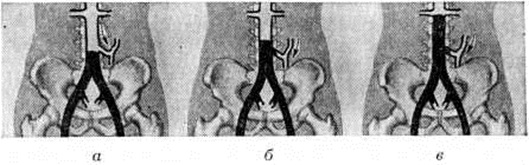

В зависимости от проксимального уровня окклюзии брюшной аорты выделяют 3 варианта Лериша синдром (рисунок 1): низкая окклюзия (А) — дистальнее нижней брыжеечной артерии; средняя окклюзия (Б) — проксимальнее нижней брыжеечной артерии и высокая окклюзия (В) — сразу дистальнее или на уровне почечных артерий. В зависимости от поражения дистального сосудистого русла целесообразно выделять 4 типа (рисунок 2): I тип — поражение аорты и общих подвздошных артерий; тип — поражение аорты, общих и наружных подвздошных артерий; тип — к изменениям при II типе присоединяется поражение поверхностной бедренной артерии; IV тип— дополнительно поражены сосуды голени. При всех типах поражения дистального сосудистого русла выделяется вариант «а» — с проходимой глубокой артерией бедра и вариант «б» — имеется стеноз или окклюзия устья этой артерии. Следует отметить, что при этом имеется в виду не только окклюзия (полная облитерация) сосуда, но и резкие стенозы (более 75% диаметра). Поражение дистального сосудистого русла у одного и того же больного может быть асимметричным. Различают 4 степени ишемии: I — начальные проявления; IIA — появление перемежающейся хромоты через 300—500 метров ходьбы; II Б — появление перемежающейся хромоты через 200 метров ходьбы; III — боли через 25— 50 метров ходьбы или в покое; IV — наличие язвенно-некротических изменений.

Рис. 1.

Схематическое изображение вариантов окклюзии брюшной аорты, приводящих к синдрому Лериша: а — низкая окклюзия аорты (А) — дистальнее нижней брыжеечной артерии; б — средняя окклюзия аорты (Б) — проксимальнее нижней брыжеечной артерии; в — высокая окклюзия аорты (В) — сразу дистальнее почечных артерий; черным цветом показан облитерированный сегмент аорты и подвздошных артерий; стрелкой указано направление кровотока по нижней брыжеечной артерии.

Рис. 2.

Схематическое изображение типов поражения брюшной аорты и артерий нижних конечностей, приводящих к синдрому Лериша: I тип — поражение бифуркации аорты и общих подвздошных артерий; II тип — поражение аорты, общих и наружных подвздошных артерий; III тип — поражение аорты, общих, наружных подвздошных и поверхностных бедренных артерий; IV тип — поражение аорты, общих и наружных подвздошных, поверхностных бедренных артерий и артерий голени; черным цветом указаны места окклюзии или стеноза артерий.